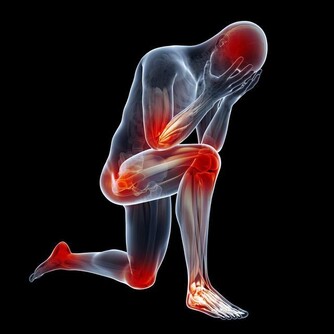

氣溫驟降時,腦血管疾病發病者明顯增加。劉霞發病時,正好遇到兩大誘因,一是天氣轉冷,二是深夜用熱水泡腳,都可能令血管受到強烈刺激,一定程度上誘發疾病。因此,有腦血管基礎性疾病的市民,近期應注意防寒保暖,避免身體遭受冷暖刺激。少用過熱的水洗澡、泡腳,少喝酒,避免情緒激動。同時,還應定時對身體進行全面檢查。

這類病人泡腳時要格外小心,一是水溫不可過高,二是泡腳時間不能過長,因為用熱水泡腳后,會迅速導致人體血管擴張,全身血液會由重要臟器流向體表,因此很容易使心臟、大腦等重要器官缺血缺氧,因此對於有心臟病、低血壓的人群來說,就會增加他們發病的危險。